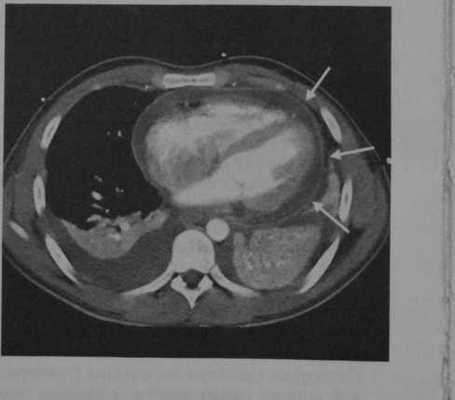

Вторичный тяжелыйперикардит как осложнение тонзиллярного абсцесса у женщины 20 лет. После введенияконтраста на КТ определяется выпот в полость перикарда, выраженное усиление перикарда (стрелки), плевральный выпоти двусторонние ателектазыв базальных сегментах легкихв связи с ОСИ.